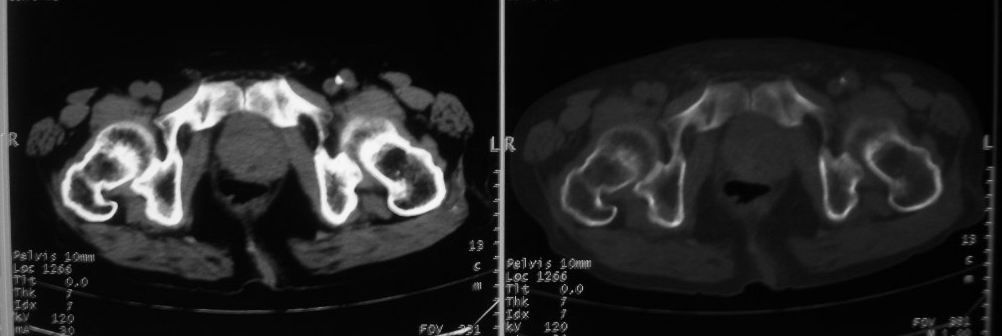

以下是引用zjzjr在2008-10-3 12:59:00的发言:[br]前列腺癌伴左髂骨\\腰椎转移可能性大.

以下是引用卜一在2008-10-3 13:40:00的发言:[br]前列腺癌!左髂骨\\腰椎转移?建议行全身骨扫描!

以下是引用深泽交通医院在2008-10-3 15:33:00的发言:[br]前列腺实性增大伴分叶状,与包膜间隙境界不清;椎体松质区间结节样密度影,考虑:前列腺癌,并椎体成骨性转移